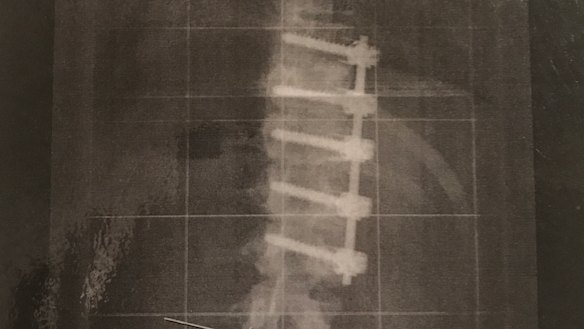

Featonby earned the name 'titanium woman' due to the titanium rod and five screws in her spine, inserted as part of an anterior fusion to correct severe scoliosis as a teenager.

Featonby has a titanium rod and five screws in her spine as the result of severe scoliosis.